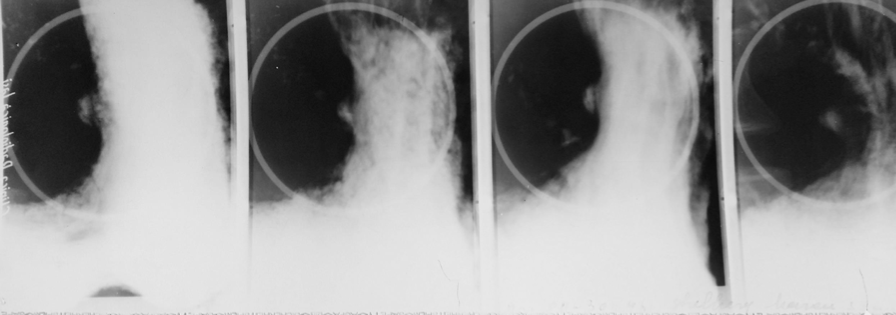

Achalazia cardiei